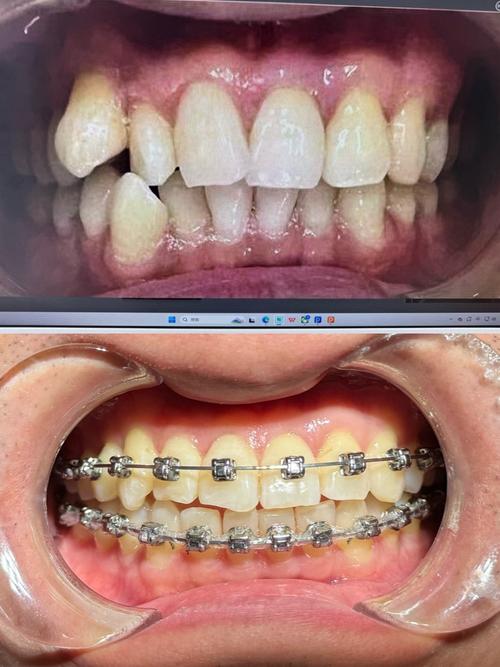

牙齿矫正的原理是利用外力(如托槽、隐形牙套)施加轻柔、持续的力,引导牙齿在牙槽骨中缓慢移动,这一过程涉及牙齿、牙根、牙槽骨、颌骨关系等多重因素,仅通过肉眼观察或口腔检查无法全面掌握潜在风险,拍片子则能提供“透视级”的详细信息。

通过全景片(曲面断层片),可清晰观察全口牙齿的数量、形态及位置,包括是否存在“多生牙”(额外牙齿)、“缺失牙”(先天性或后天性缺失)、“埋伏牙”(未萌出的牙齿,如阻生智齿)等异常,若存在埋伏牙,需判断其位置、方向是否会影响矫正中牙齿的正常移动,或是否需要提前手术拔除;若存在多生牙,可能占据正常牙齿的生长空间,导致牙列拥挤,需在矫正前处理,还能观察牙根形态是否正常(如弯曲、短根),牙根周围是否有吸收或病变,这些因素直接影响牙齿移动的稳定性和安全性。